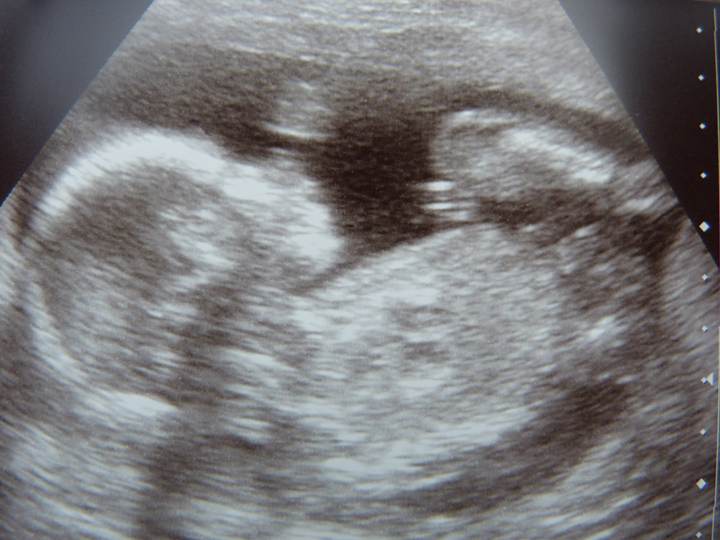

19 weeks u/s

Thanks Rockstar, in the second picture the tech put an arrow pointing at the boy bits, and in the third picture I think the winky is the bobbly bit inbetween the legs but I'm confused as there are kind of two together and then a third mark to the right. Maybe that is part of the foot or something else?

I tried to compare it to my other sons scans but there literally aren't any gender clues on them although we were told boy at the scans.

That's a boy without a doubt! Nice side view of boy bits (scrotum and penis)!!